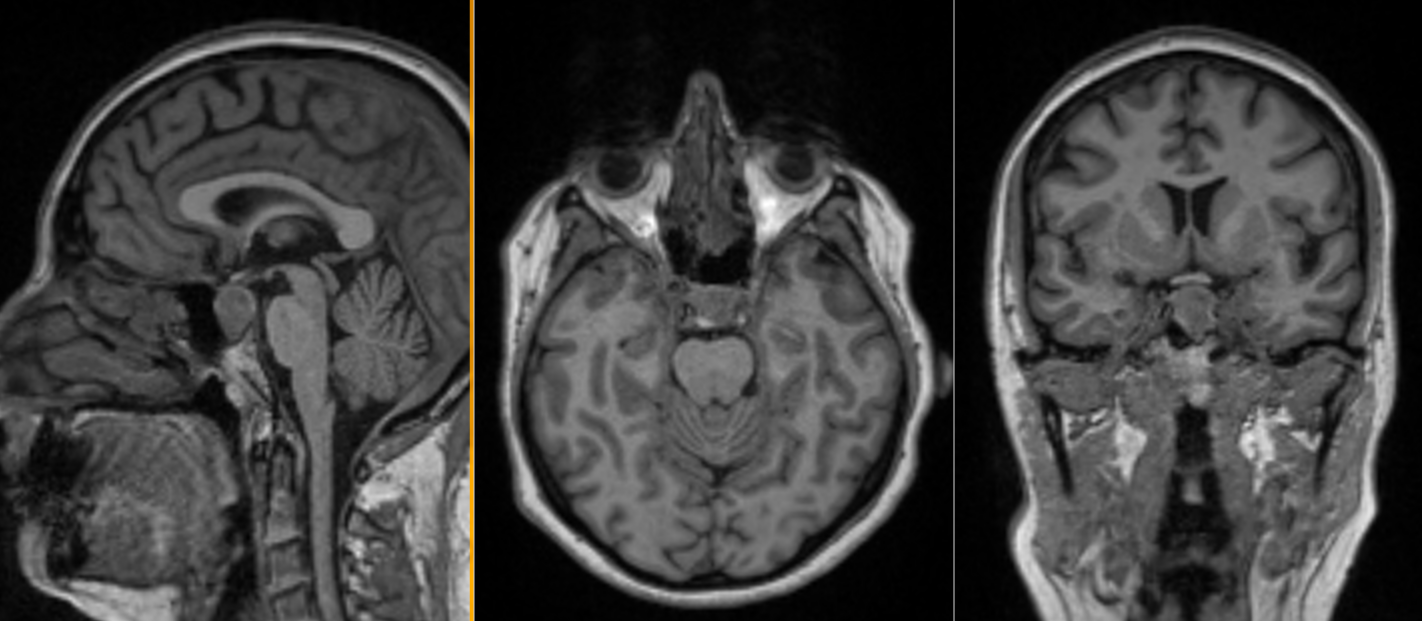

- Apoplexia pituitară reprezintă o complicație rară dar redutabilă a evoluției unui adenom hipofizar; se datorează unor modificări vasculare – un infarct al adenomului urmat de hemoragie, ceea ce determină creșterea bruscă și semnificatvă în volum a tumorii cu efect de masă pe nervii optici și structurile din jur. Clinic se caracterizează prin simptome brusc instalate și violente: cefalee, vărsături, tulburări de echilibru, scăderea bruscă a vederii. Reprezintă o urgență chirurgicală – doar operația efectuată rapid poate remite simptomele și salva vederea

Apoplexie pituitara

- RMN cerebral cu contrast este metoda de elecție pentru vizualizarea tumorii.

- Macroadenoamele hipofizare apar ca mase tumorale cu priza de contrast localizate la nivelul șeii turcești, eventual cu extensie superioară (supraselară) spre nervii optici sau, mai rar, inferioară, în sinusul sfenoid; de multe ori ele se pot extinde și lateral, în sinusurile cavernoase (structuri vasculare venoase formate în grosimea meningelui care mărginește lateral șaua turcească, prin care trec arterele carotide interne).